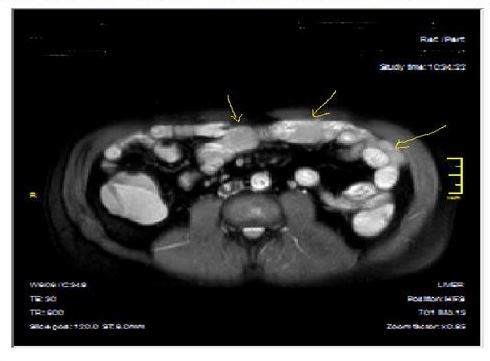

Figure 2a.Concentric luminal narrowing, mural and transmural involvement of terminal ileum due to Crohn’s disease in T2W coronal sequence after OCA application.

Figure 2b.Curvi-lineer, diffuse peripheral enhancing bowel wall in the terminal ileum on axial T1W post-contrast image.